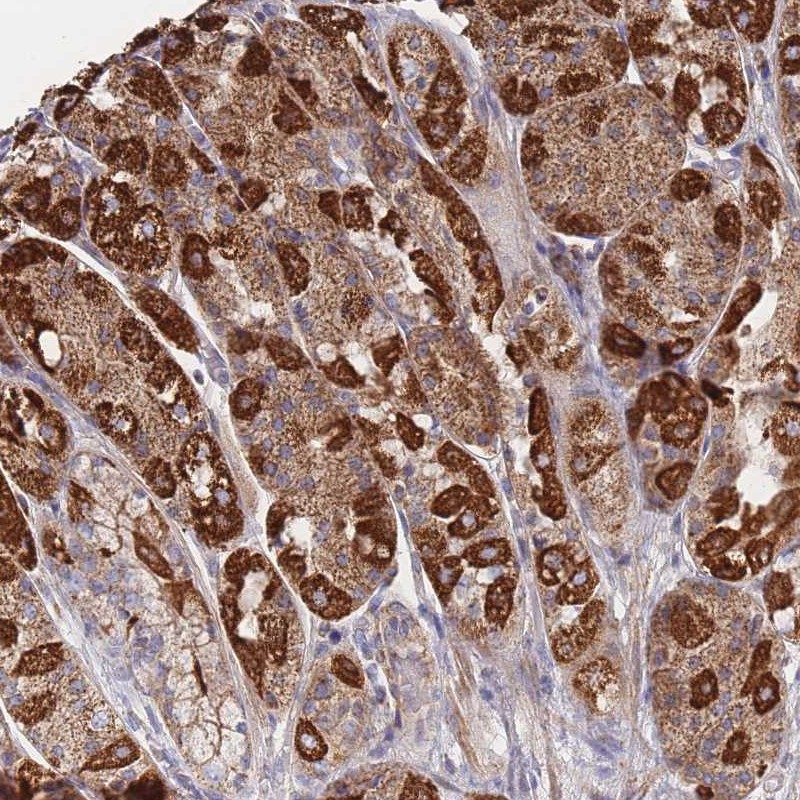

Immunohistochemical staining of human stomach, upper shows strong granular cytoplasmic positivity in glandular cells.